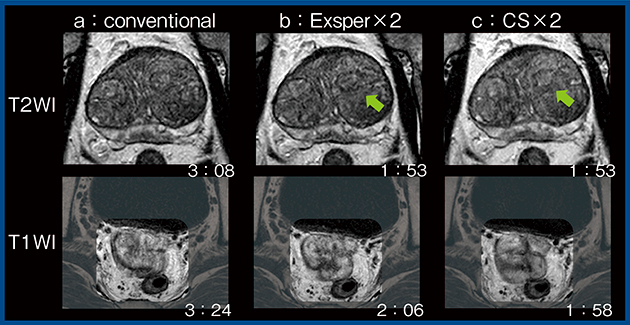

図4は,SPEEDER とExsperの比較である。位相エンコード方向が体軸方向(HF)のため,SPEEDER 2倍速の画像では,no wrap(NW)を1.2と短くすると,撮像時間は短くなるものの画像中心に展開アーチファクトが生じる(b↓)。一方,Exsperは展開精度が高いため,NW1.2の3倍速においても展開アーチファクトが生じず,より短時間での撮像が可能となる(c)。

図5は,前立腺の評価目的に撮像されたT2強調画像(上段)とT1強調画像(下段)であるが,従来法(SPEEDER:a)と比較して,Exsper(b)とCS(c)ではより短時間の撮像でモーションアーチファクトが低減している。上段のT2強調画像における前立腺移行域を詳細に見ると,Exsperでは被膜などの微細な構造をより明瞭に描出していることを確認できる(↑)。また,下段のT1強調画像では,Exsperの方が腸管辺縁を鮮明に描出している。

以上より,CSやExsperでは撮像時間の短縮によってモーションアーチファクトが低減され,従来法よりも画質が向上すると考える。CSは位相エンコード方向に生じるモーションアーチファクトに強く,一方,Exsperは鮮明な画質を保ちつつ高速化でき,特に淡いコントラストで有用な可能性がある。なお,CSとExsperの使い分けは,今後の検討課題である。

図4 SPEEDERとExsperの比較

図5 従来法,Exsper,Compressed SPEEDERの比較(前立腺)